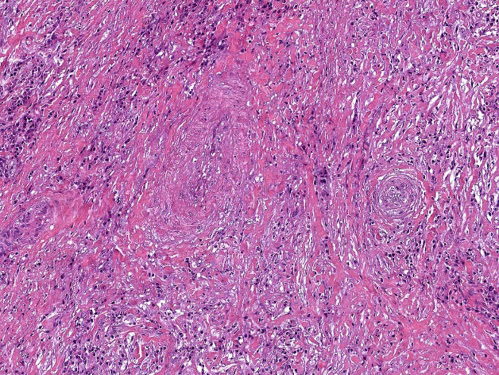

5. Fig. 5. The histological picture of the postoperative material of the thyroid gland. | |

| Subject | ||

| Type | Other | |

View

(113KB)

|

Indexing metadata ▾ | |